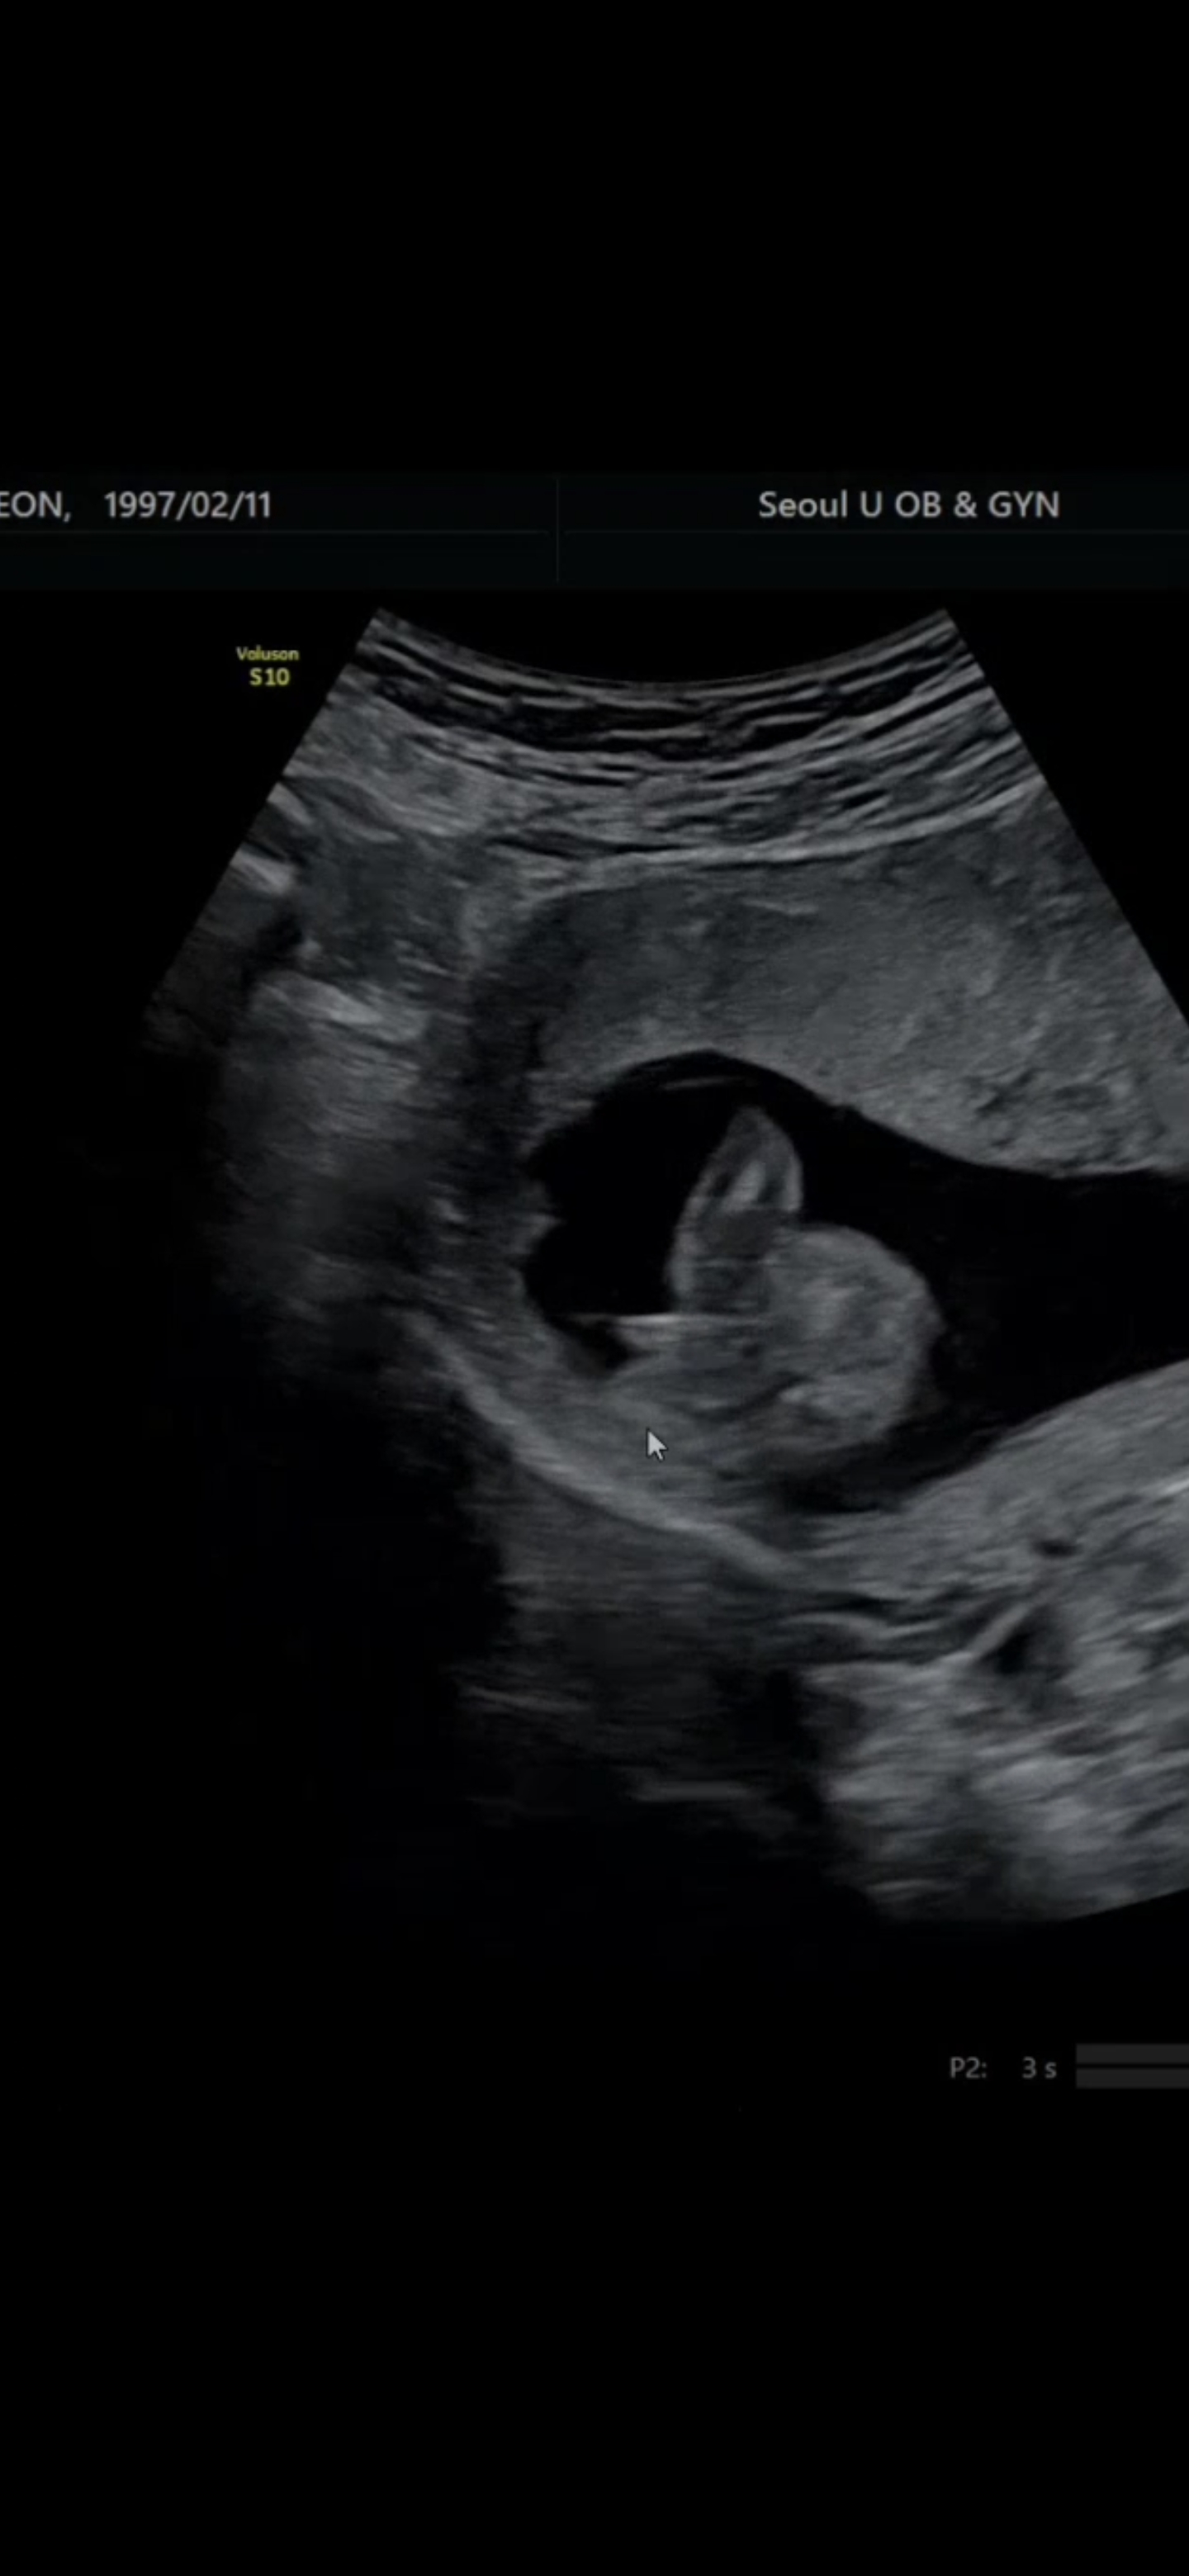

15주 초음파 성별 봐주세요!

기본적으로는 안 보이다가 특정 각도에서는 탯줄인지... 성기인지 모르겠는 게 보이네요ㅠㅠ 다리가 곧게 편 영상에선 안 보여서 이렇게 올려요! 탯줄일까요, 성기일까요?